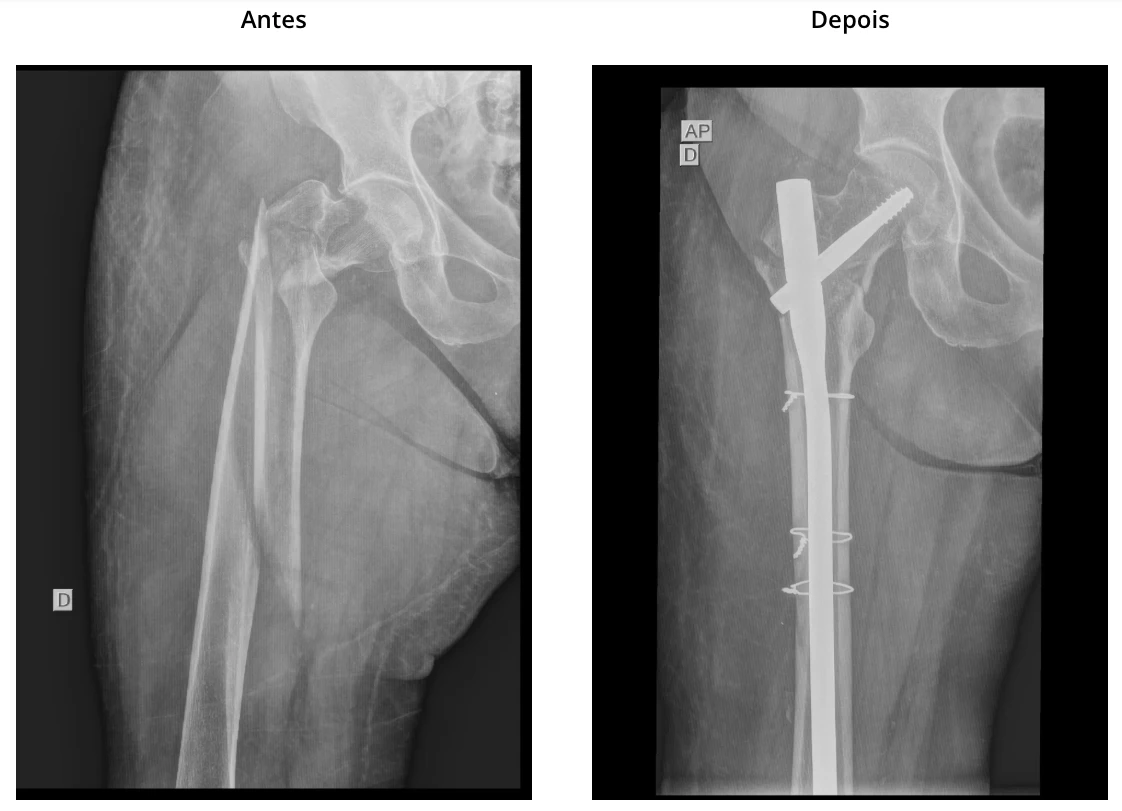

Foto de Fratura do fêmur proximal

As fraturas do fêmur proximal, são mais comuns em idosos e geralmente resultam de quedas da própria altura ou traumas de baixa energia, ocorrem devido à fragilidade óssea associada à osteoporose que é comum nessa idade. O tratamento é predominantemente cirúrgico e está bem estabelecido o benefício de realizar o mais breve possível, principalmente para restaurar a mobilidade e minimizar o impacto na qualidade de vida.

O manejo da fratura do fêmur proximal pode envolver cirurgias de fixação com hastes intramedulares do fêmur proximal ou a substituição do quadril por artroplastia, a depender da localização e característica da fratura. A reabilitação, que inclui fisioterapia e exercícios de fortalecimento muscular, é fundamental para a recuperação. Além disso, medidas preventivas, como a suplementação de cálcio e vitamina D, e exercícios de equilíbrio, são essenciais para reduzir o risco de novas quedas e fraturas futuras.